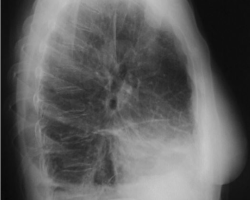

Femme de 65 ans

ATCD : tabagisme sevré, néo du sein droit traité par chirurgie et radiothérapie, exposition à l’amiante

Douleurs thoraciques droites + dyspnée d’effort + toux sèche

Abolition du murmure vésiculaire de la base droite + perte de poids